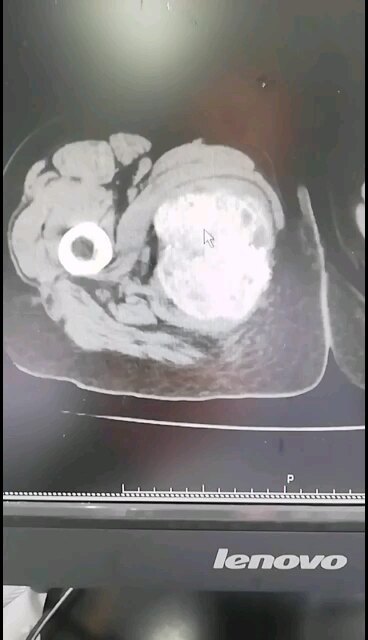

骶骨骨巨细胞瘤

刘铁龙无职称 上海长征医院 骨科